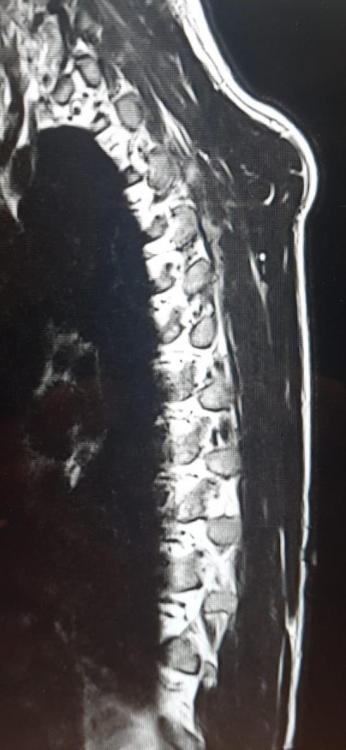

MRT HWS und BWS, was ist da zu sehen?